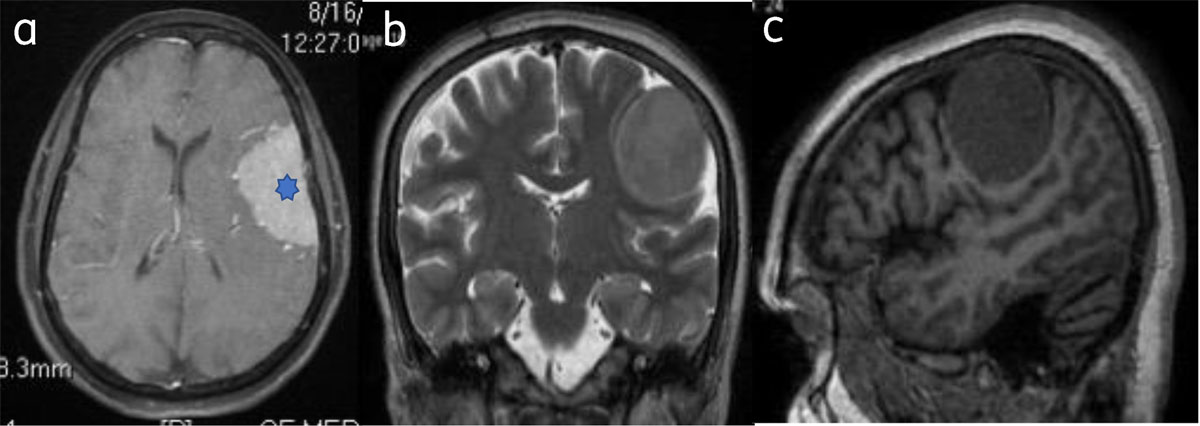

Classical Meningioma are extra axial and broad based, appear hypo-isointense on T1WI and iso-hyperintense on T2WI to the gray matter, and show intense homogenous contrast enhancement (Figure 1).

Figure 1

Classical meningioma: – (a) Axial post contrast image show enhancing broad based extra-axial lesion (star). Lesion is isointense on T2W (b) and T1W (c) to the gray matter.